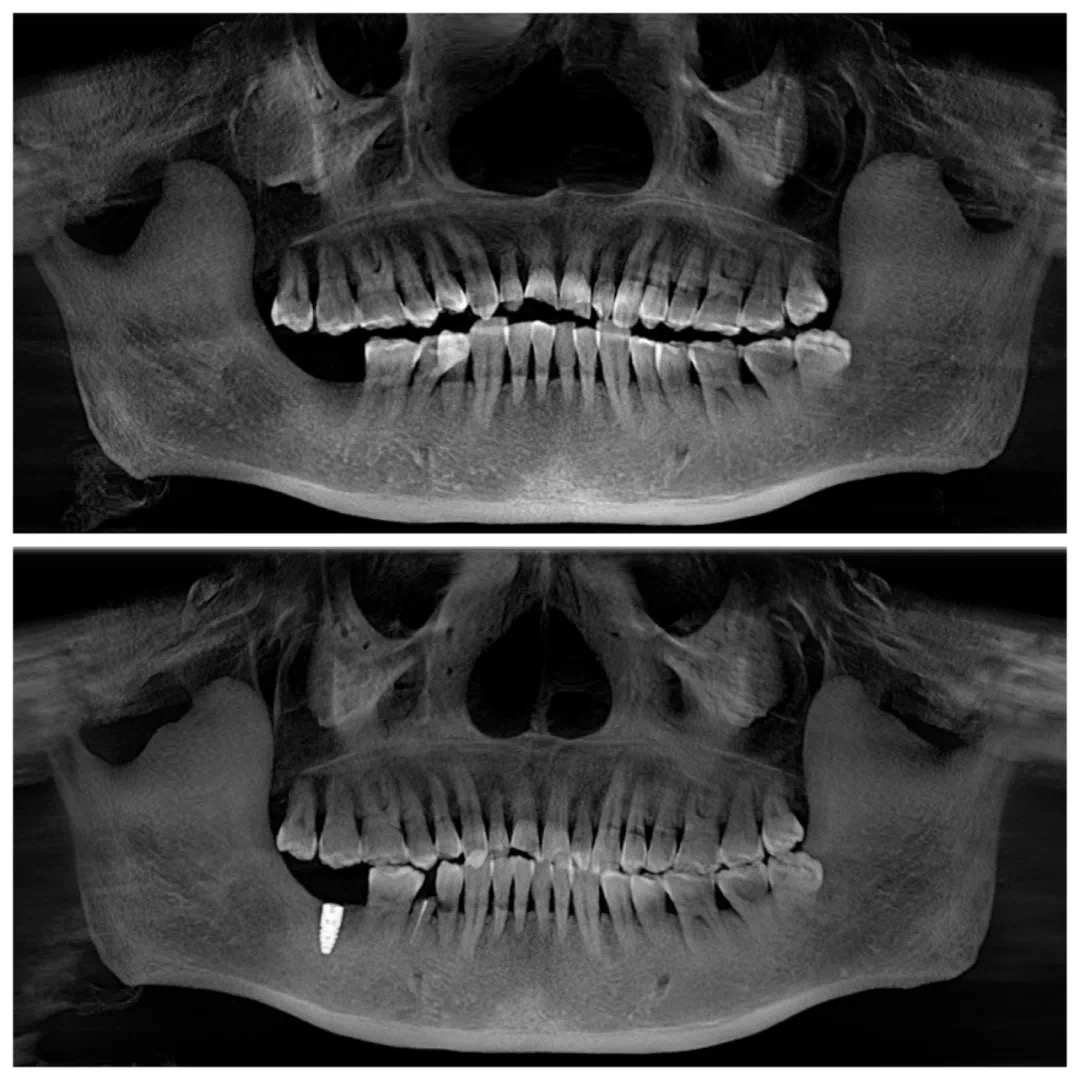

首先进行初步的检查,通过数字化口扫设备和CBCT全景影像得到了白叔叔口内的详细数据。

在进行了全面的术前检查和评估之后,医生会将完整数据上传到UNIC全息数字化会诊系统中,以数字化全息影像为基础的方案设计更形象、更易懂。

在UNIC数字化种植方案设计中心,杨勇主任耐心的为白叔叔讲解。根据全景牙片可以看到,白叔叔的右侧下颌第二磨牙缺失,影响右侧咀嚼功能。

左侧的牙齿状态较好,因此叔叔也更加信任左侧的牙齿,长时间的偏侧咀嚼,超负荷咀嚼导致左侧牙周状况比较糟糕,关节也出现隐患,胃肠消化也有问题。

CBCT三维立体全景影像片及术前模拟